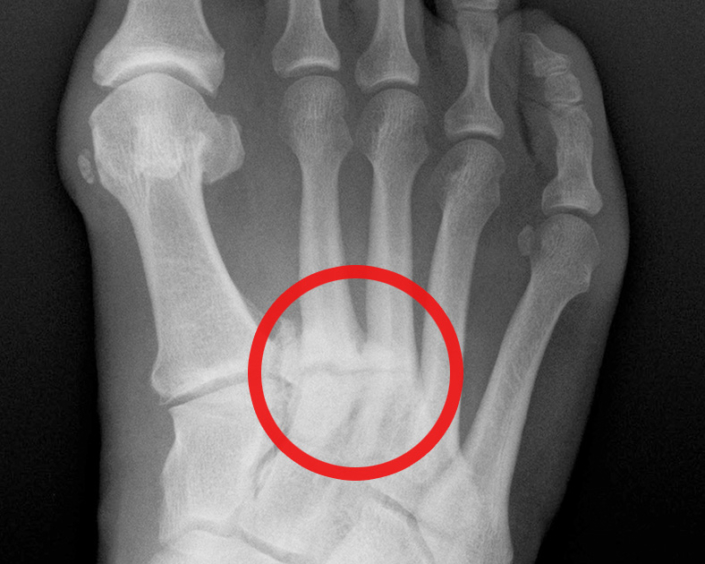

Dabei äußert sich der Bruch meist als Knochenödem oder als sichtbare Frakturlinien. Ein sogenannter Ermüdungsbruch war die Ursache der sich chronifizierenden Schmerzen im Fuß, die jeden Schritt zur Qual machten und sich selbst über Nacht nicht mehr besserten Ein Ermüdungsbruch im Fuß äußert sich durch deutlich spürbare Symptome

Ermüdungsbruch im Fuß Symptome & Schmerzen behandeln. Im Bereich des Fußes treten Stressfrakturen am Mittelfuß oder an der Fußwurzel auf Ein sogenannter Ermüdungsbruch war die Ursache der sich chronifizierenden Schmerzen im Fuß, die jeden Schritt zur Qual machten und sich selbst über Nacht nicht mehr besserten